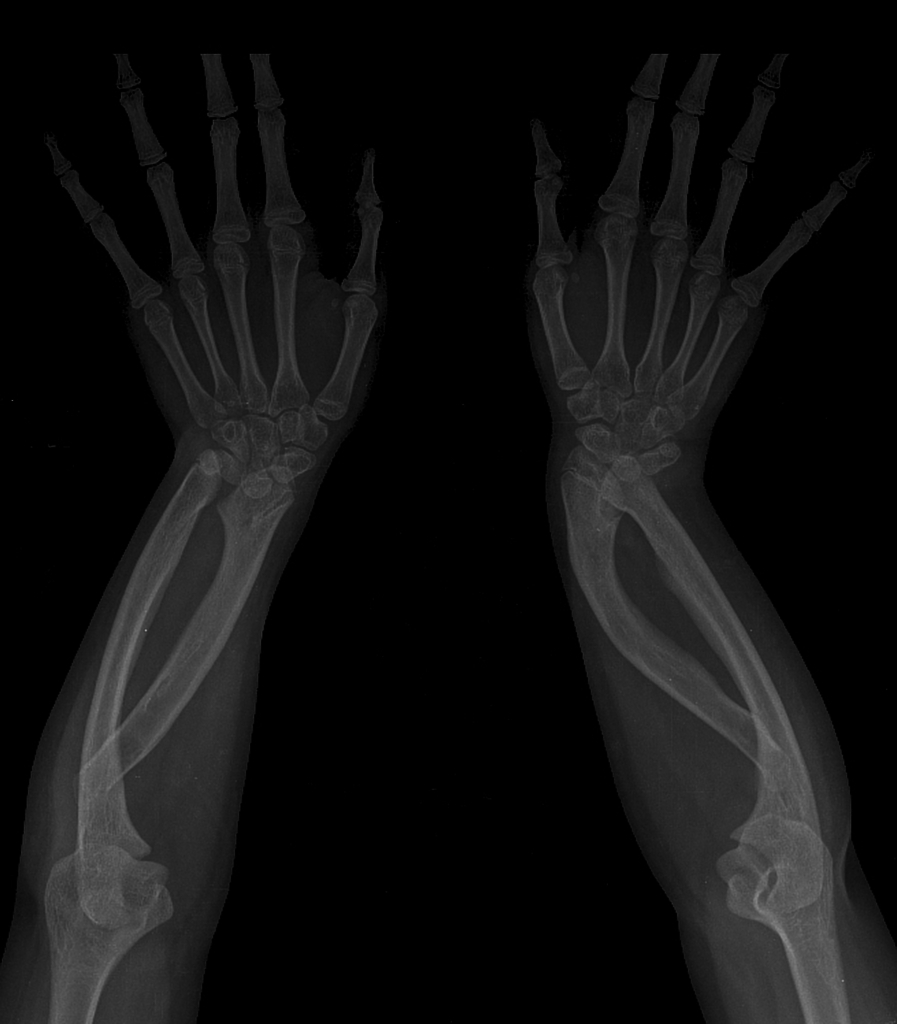

Madelung deformity. It comprises: (a) short distal radius, which shows a dorsal and ulnar curve;

(b) triangular shape of the distal radial epiphysis;

(c) premature fusion of the ulnar side of the distal

radial epiphysis;

(d) dorsal subluxation of the distal ulna;

(e) enlarged and distorted ulnar head; and

(f) wedging of the triangular-shaped carpus between the distal radius and ulna.

1. Isolated – bilateral > unilateral. Asymmetrical. Predominantly adolescent or young adult women.

2. Dyschondrosteosis (Leri–Weil disease) – bilateral with mesomelic limb shortening. AD. Predominantly men.

3. Diaphyseal aclasis.

4. Turner’s syndrome*.

5. Post-traumatic.

6. Postinfective.

Pseudo-madelung. Refers to increased radial inclination (i.e. ulnar tilt) of the distal radius but with negative ulnar variance and the absence of other typical features of Madelung deformity

hereditary multiple exostoses post-trauma, e.g. physeal injuries rickets enchondromatosis - Ollier disease 1 post-inflammatory or infectious arthritis achondroplasia mucopolysaccharidoses, e.g. Morquio syndrome, Hurler syndrome